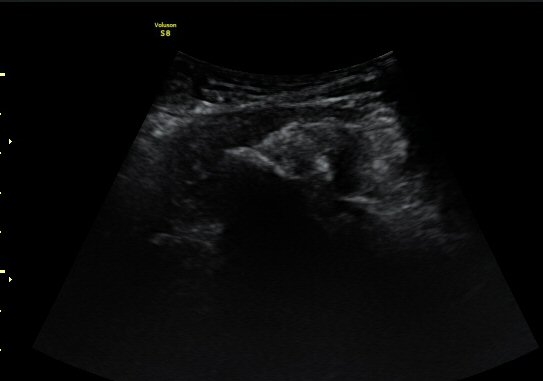

¼±»óŽÃÊÀÚ¸¦ ÀÌ¿ëÇÑ °Ë»ç¿¡¼­ ÀüÇÏÀ屨ÀÇ ´ëÅðÁ÷±Ù ±â½ÃºÎ¿¡ ¼®È¸È­ À½¿µÀÌ ¶Ñ·ÈÈ÷

°üÂûµÊ(»çÁø 4, 5).